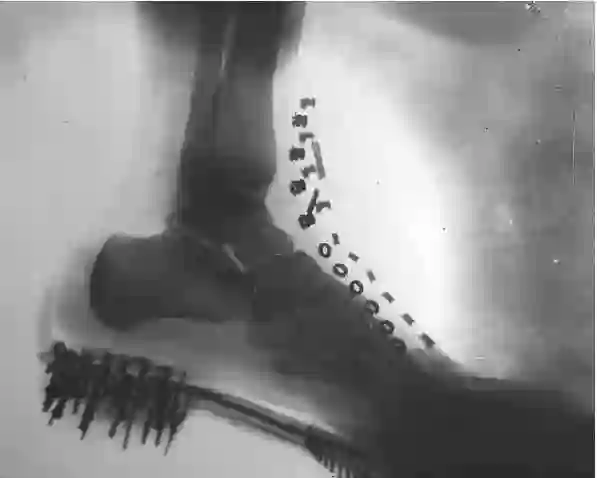

特斯拉用自己的身体试验X射线,这是他拍摄的脚部影像图